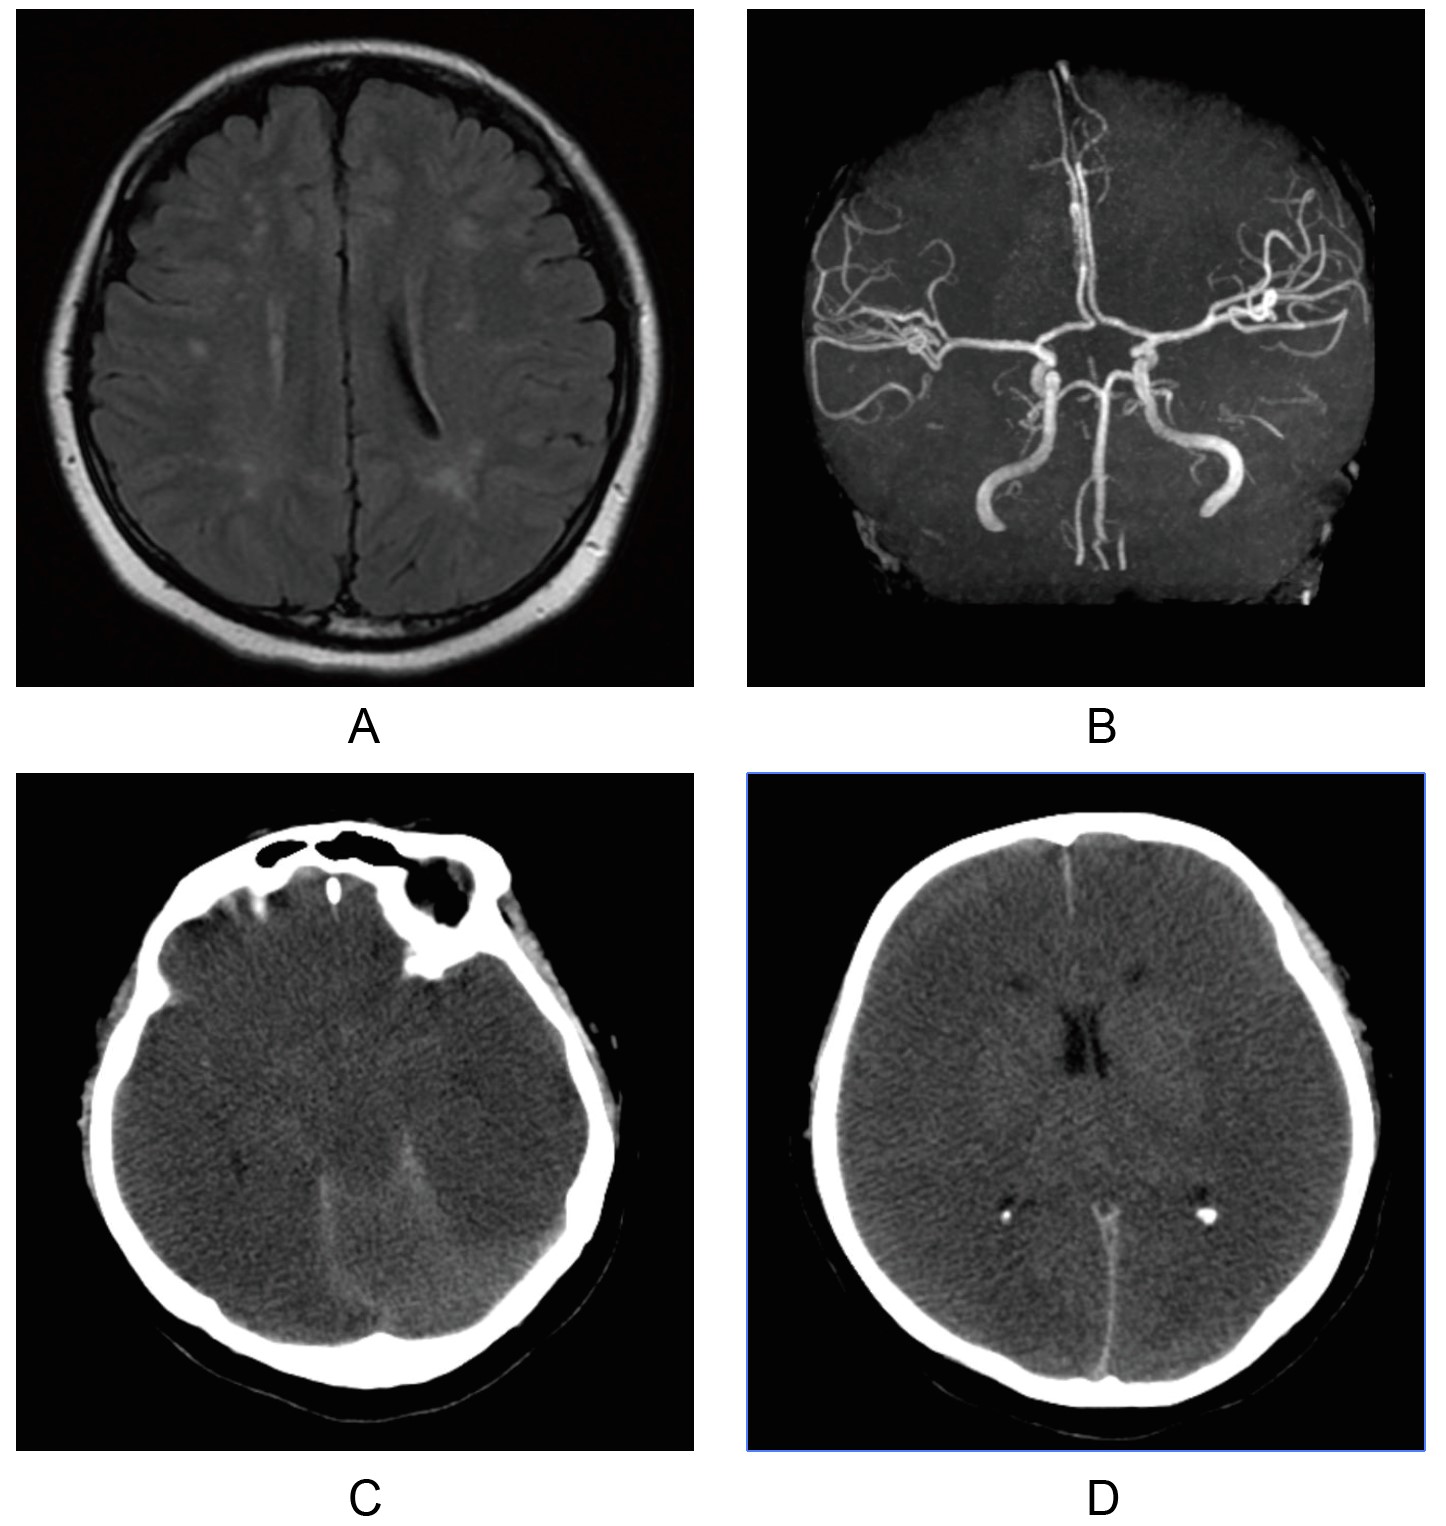

On the first night, the patient suffered from poor sleep, and gradually increasing apathy, intermittent twitching of hands and urinary incontinence during the night were noticed. Departments of psychology, gastroenterology and neurology were called in for consultations to rule out hepatic encephalopathy and primary neurological disorders that may cause psychiatric symptoms. No history of hepatic disease, negative hepatitis virus test and mildly elevated of ALT, suggested a small possibility of hepatic encephalopathy. Head magnetic resonance imaging (MRI) suggested scattered cerebral lacunar infarctions or demyelinating lesions, and magnetic resonance angiography (MRA) showed a finer intracranial segment of the right vertebral artery, in Figure 1A and 1B. Magnetic resonance venography (MRV) showed no abnormality. Further immunological examinations ruled out autoimmune encephalitis.

Figure 1

Figure 1: Head MRI and CT. (A) Head MRI, scattered cerebral lacunar infarctions or demyelinating lesions. (B) Head MRA, a finer intracranial segment of the right vertebral artery. (C) Head CT, a diffuse cerebral edema. diffuse hypodensity of the intracerebral parenchyma, indistinct demarcation of the gray and white matter. (D) Head CT, minor subarachnoid hemorrhage, slightly compressed and narrowed ventricles, increased density of the cerebral falx and cerebellar curtain, and centered midline structures can be seen. MRI: magnetic resonance imaging; CT: computed tomography.

On the 5th day, the patient had another convulsion with decreased oxygen saturation, and unequal bilateral pupils, without pupillary light reflex. Head CT suggested diffuse cerebral edema and minor subarachnoid hemorrhage, in Figure 1C and 1D. On the 6th day, the patient’s plasma ammonia concentration was repeatedly elevated and fluctuated between 133–800 μmol/L, as detailed in Figure 2, as OTCD was considered, LOLA treatment was stopped. AST and ALT did not show significant abnormalities, as shown in Figure 3. Further tests were recommended again and were agreed.